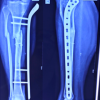

This prospective observational study was conducted at a tertiary-level trauma center in Delhi over 18 months after obtaining approval from the respective institutional ethics committee. Written informed consent was obtained from all participants before inclusion. Thirty skeletally mature patients (aged ≥18 years) presenting with closed diaphyseal or diaphyseo-metaphyseal femoral fractures who were managed with closed antegrade IMN were enrolled consecutively. Patients with pathological fractures, compound injuries, old neglected fractures, abnormal femoral anteversion in the contralateral limb, uncontrolled systemic comorbidities, or pregnancy were excluded from the study. All procedures were performed under spinal anesthesia with the patient positioned supine on a fracture table. A standard lateral approach was used to access the proximal femur. Closed reduction was achieved using traction and image intensifier guidance. Rotational alignment was approximated intraoperatively by evaluating the cortical diameter and lesser trochanter profile compared to the contralateral limb. Post-operative assessment of femoral torsion was performed using CT. The rotational alignment was measured using the Jeanmart method [6], which calculates the angle between a line drawn along the posterior condylar axis distally and a line through the femoral neck axis proximally (Fig. 1).

Figure 1: Computed tomography (CT)-based measurement of femoral malrotation using the Jeanmart method. Axial CT slices at the femoral neck and condylar levels demonstrating angle α on the operated side and angle β on the contralateral side; the difference (α-β) represents the degree of femoral malrotation.